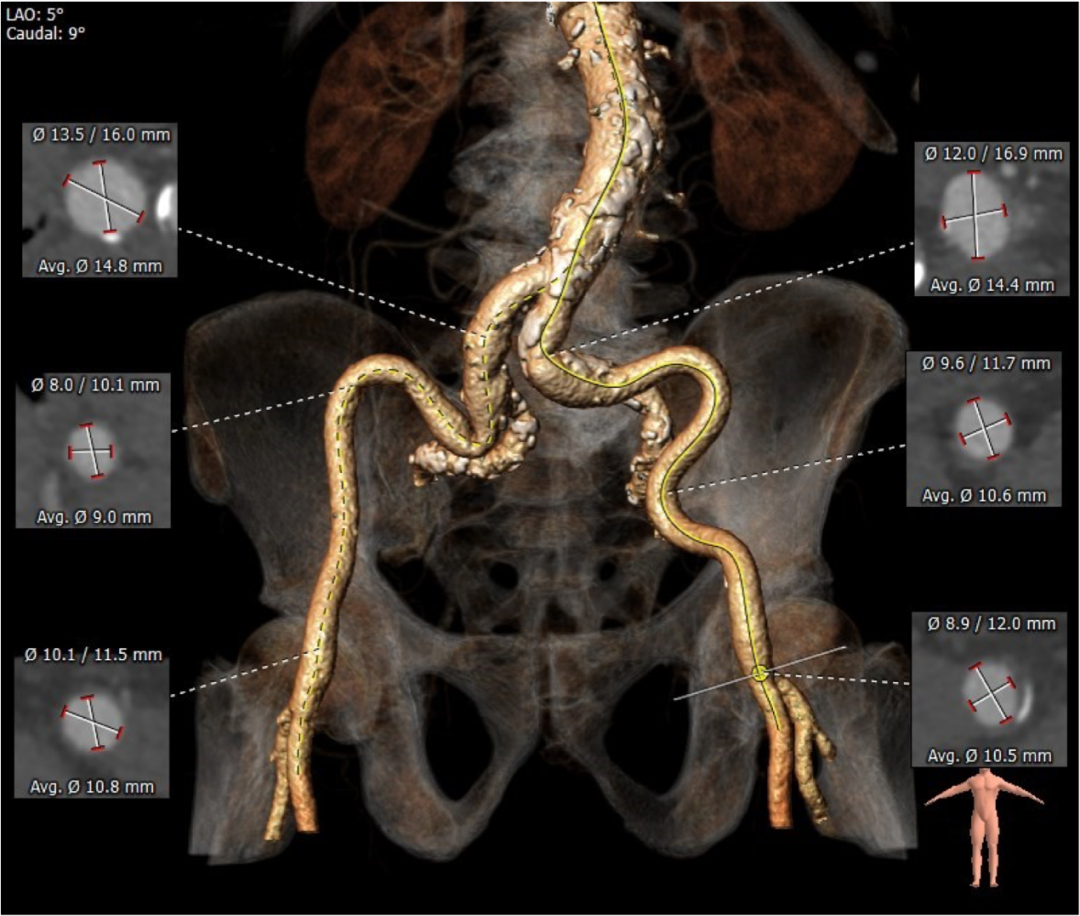

血管外周入路评估: